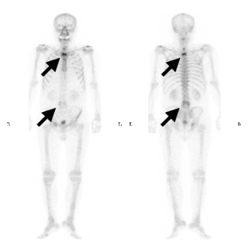

뼈스캔은 방사성동위원소를 사용하여 뼈로의 전이 유무를 확인할 수 있습니다.

[ 경추, 흉추, 및 요추에 다발성 골전이 병변이 관찰되는 뼈동위원소 검사 ]